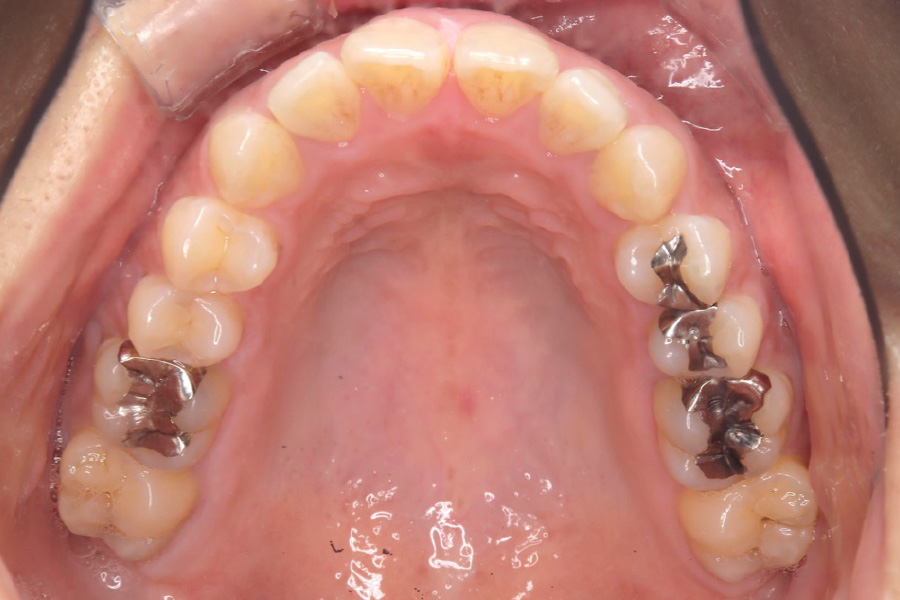

治療前